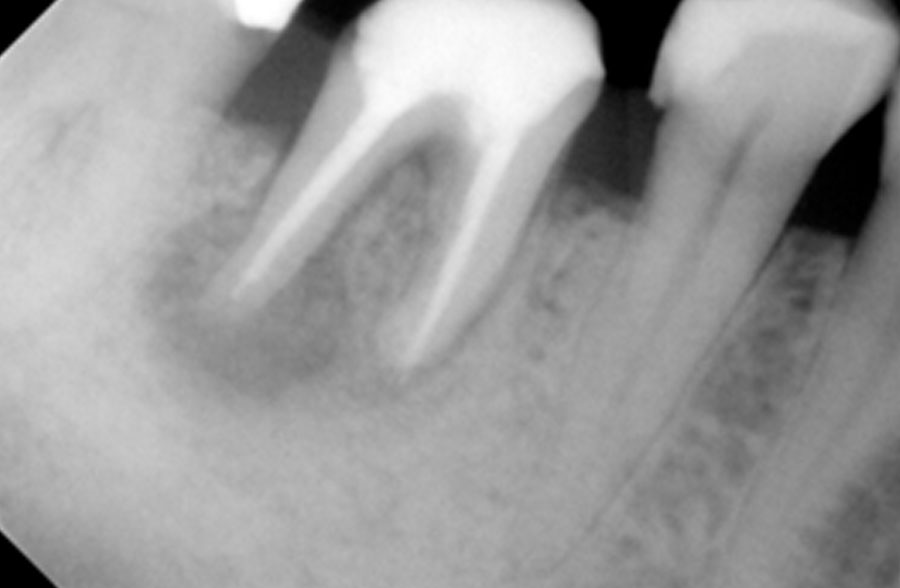

Χρόνια φλεγμονώδης περιακρορριζική βλάβη, κυρίως,

λόγω ενδοδοντικής αιτιολογίας. Μετά την ενδοδοντική θεραπεία

ακολούθησε περιοδοντική θεραπεία.

Δύο χρόνια μετά, παρατηρείται πλήρης εξαφάνιση της βλάβης.